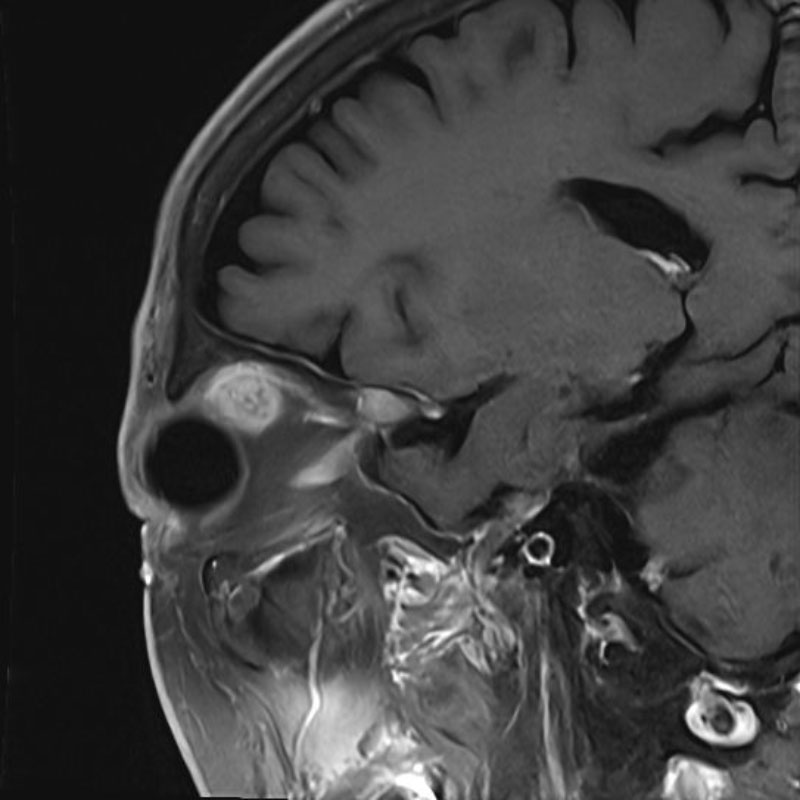

症例 '25年11月

No.

696

※ 画像をクリックすると拡大表示します。症例No.は平成29年から起算しています。

年_番号

手術年月

患者年齢

’25_98

'25年11月

70代

病名

術式

備考

眼窩腫瘍

頭蓋内腫瘍摘出術

術中写真

摘出 前

摘出 中

摘出 後